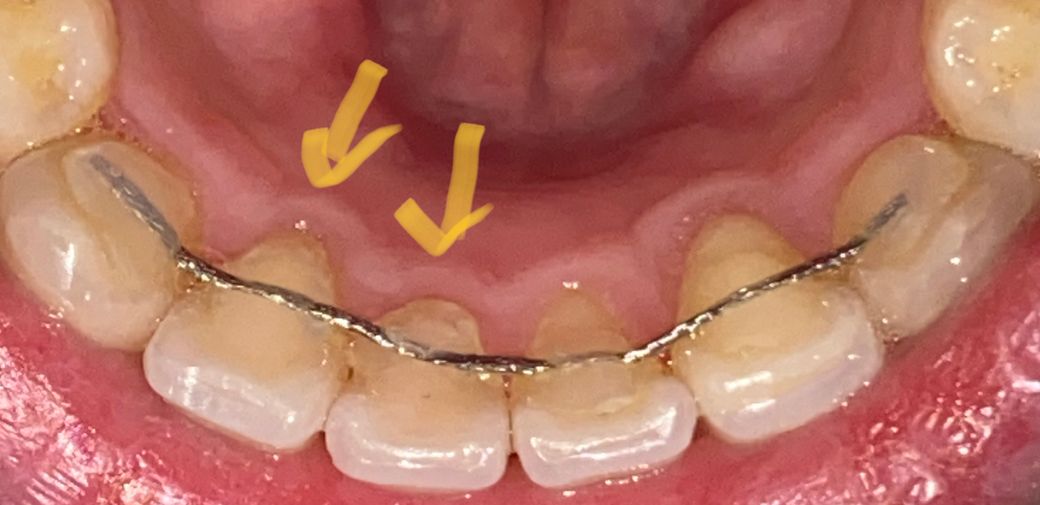

하악 치아 뒤쪽에 고정식 유지장치를 붙여놓은지 7년이 되었는데요

최근 잇몸이 많이 퇴축되고 있음을 알게되었습니다

사진에 표시해 놓은 유지장치 레진이 잇몸과 너무 가까워서

스케일링을 해도 레진 아랫 부분 치석이 잘 제거되지 않는 것 같고 치석이나 치태도 다른 곳보다 잘 낍니다. 가끔 잇몸쪽이 빨갛게? 되기도 하구요.

잇몸 퇴축에 영향을 미칠까봐 두 개 레진만 제거했다가 새로 부착하고 싶은데